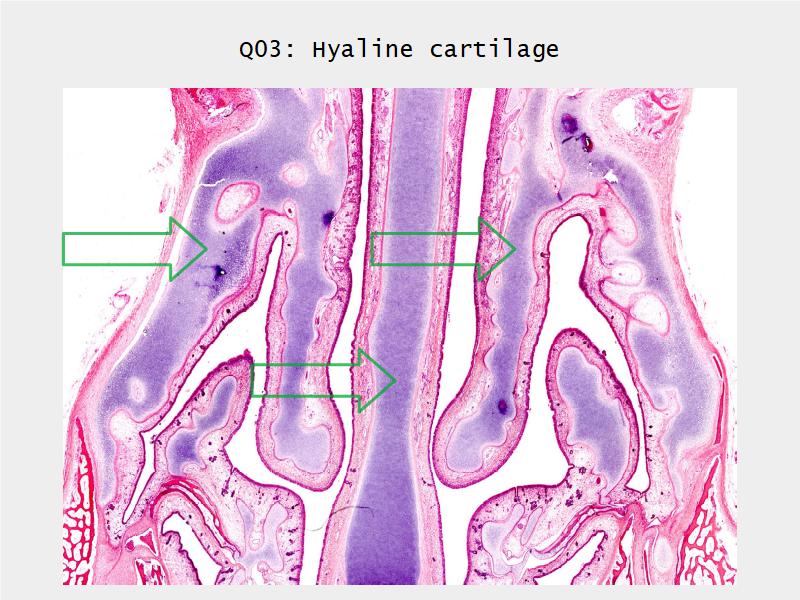

- Slide 73: Trachea